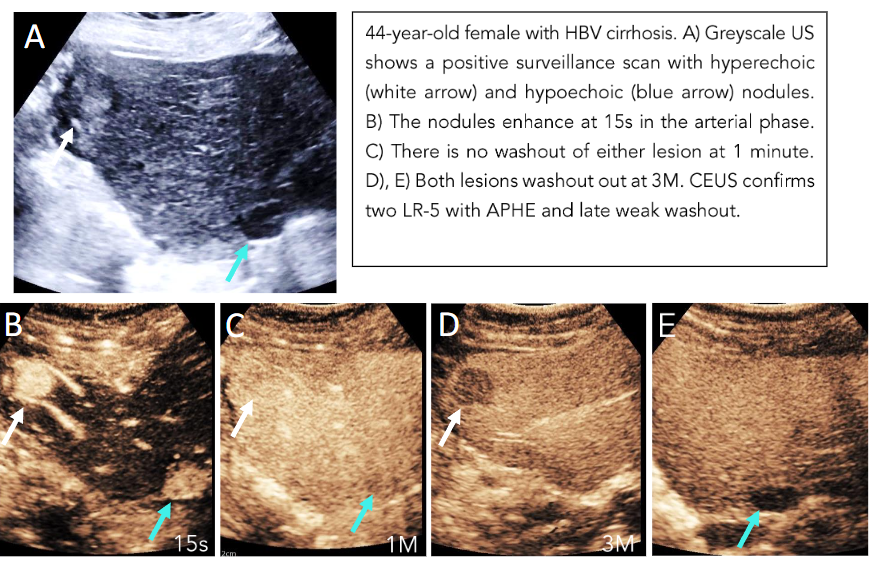

If there is any uncertainty in one without viability present in the other, the overall treatment response score is LR-TR equivocal. Here, an alternative imaging modality like MRI would be useful in clarifying the viability.

Only when there is absent viability in both intralesional and perilesional viability is the final category designated as LR-TR nonviable (Figure 12).